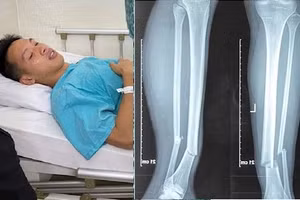

Tiền vệ Đỗ Hùng Dũng được miễn toàn bộ phí điều trị

GD&TĐ - Theo lãnh đạo Bệnh viện Đa khoa Vạn Hạnh TP.HCM, ngoài các chi phí BHYT thanh toán, bệnh viện thống nhất sẽ miễn toàn bộ chi phí phẫu thuật, chi phí nằm viện và chi phí vật lý trị liệu sau mổ cho cầu thủ này.